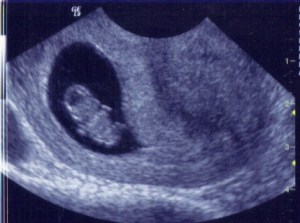

We have seen the heart beating before on ultrasounds, but it had always been too early to actually hear it. It’s a really creepy thing to hear the heartbeat of another being inside of your belly. But a relief as well. Good work baby – keep it up.